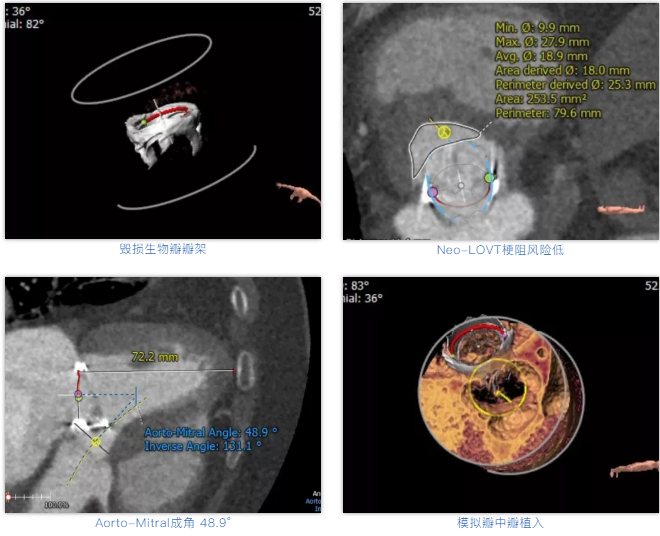

术前经详尽评估患者病情,通过CT重建测量瓣环直径、左室流出道面积。考虑到之前经房间隔入路外科换瓣,房间隔瘢痕严重,最终采用经心尖途径植入25# Renato球扩式瓣中瓣。手术顺利,瓣中瓣植入位置理想,功能表现出色,二尖瓣峰值流速由术前2m/s下降至1.4m/s,平均跨瓣压差由术前10mmHg下降至2mmHg,左室流出道压差正常,经食道超声观察无明显瓣中及瓣周返流。